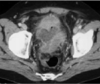

LESÃO DE ENDOMETRIOSE